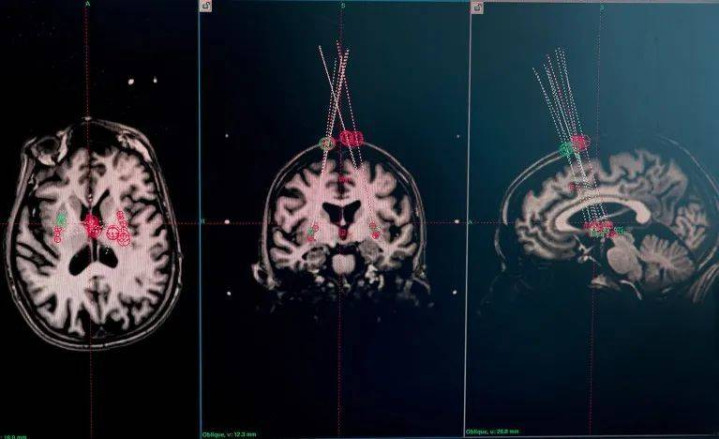

试验参与者的脑部核磁共振成像扫描被用于研究穿刺针将细胞植入的位置。图片来源:Åsa Sjöström for Nature

此外,大脑具有适应性。A9细胞通常位于黑质中,并向前脑的壳核发出投射,在那里释放多巴胺。但神经外科医生常常将祖细胞直接植入壳核,因为从外科手术的角度来说,这样更容易操作。Barker表示,大脑对胎儿组织以及对移植到“错误”部位的细胞的适应能力“相当巧妙”。